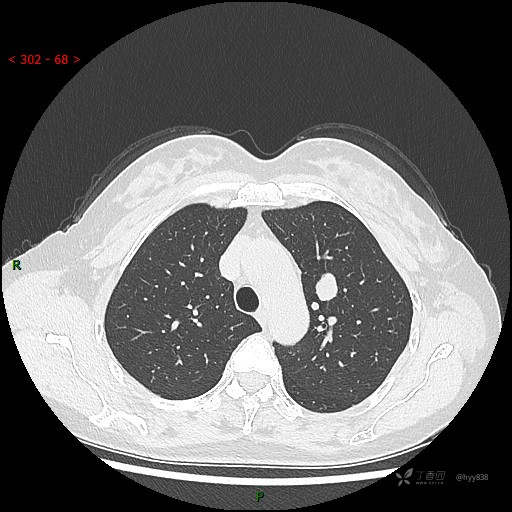

增强静脉期